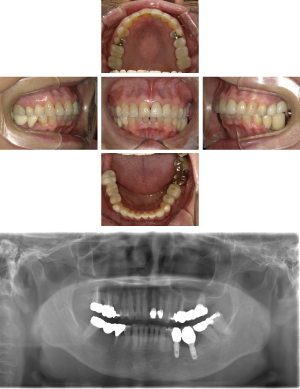

インプラント治療(左上5ソケット・GBR 右上2左上13GBR)

| 年代・性別 | 50代・男性 |

| 主訴 | 入れ歯だと咬めなくてつらい。 |

| 部位 | 上顎②1①2③4⑤Br |

| 治療期間 | 約9ヶ月 |

| 費用 | ¥1,794,100(税込) |